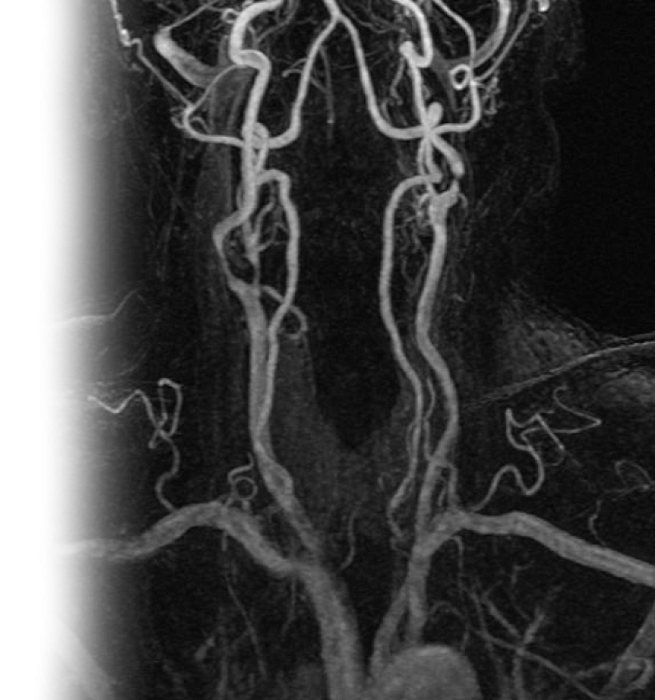

МР бесконтрастная ангиография сосудов шеи МР бесконтрастная ангиография сосудов шеи

МР бесконтрастная ангиография сосудов шеи

МР бесконтрастная ангиография сосудов шеи – важный метод исследования, который позволяет оценить состояние сосудов шеи.